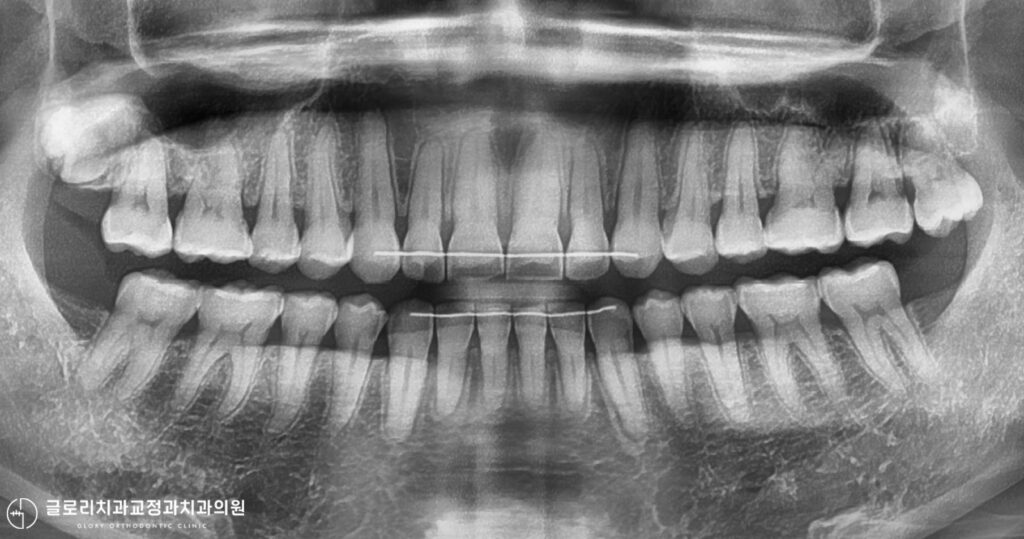

망우동 교정치과 에서 앞서 확인한 구강 모습과 골격적인 모습을 관찰해 보면,

Normodivergent pattern으로 정상적인 수직 골격 패턴을 보여줍니다.

즉, 세로로 과도하게 긴 유형(High angle)이 아니므로,

어금니 과맹출로 인한 전형적인 골격성 개방교합의 가능성은 아닌 것으로 판단됩니다.

다만, Skeletal Class II 관계를 보이고 있으며,

이는 상악의 전방 위치와 하악의 후퇴가 동반된 전후방 부조화를 의미합니다.

치아 각도를 살펴보면 상악 전치는 후방 경사를 보이는 반면,

하악 전치는 과도한 전방 경사를 보이고 있습니다.

이러한 전치부의 불균형은 절단면 간의 정상적인 수직적 접촉을 방해하게 되며,

그 결과 수직 피개(overbite)가 감소하고 전치부 개방교합이 형성된 것으로 판단됩니다.

망우동 교정치과 사진을 보면 구강 내 공간이 비교적 충분하며,

특히 상악은 필요시 사랑니 발치를 통해

추가적인 후방 여유 공간 확보도 가능한 상황입니다.